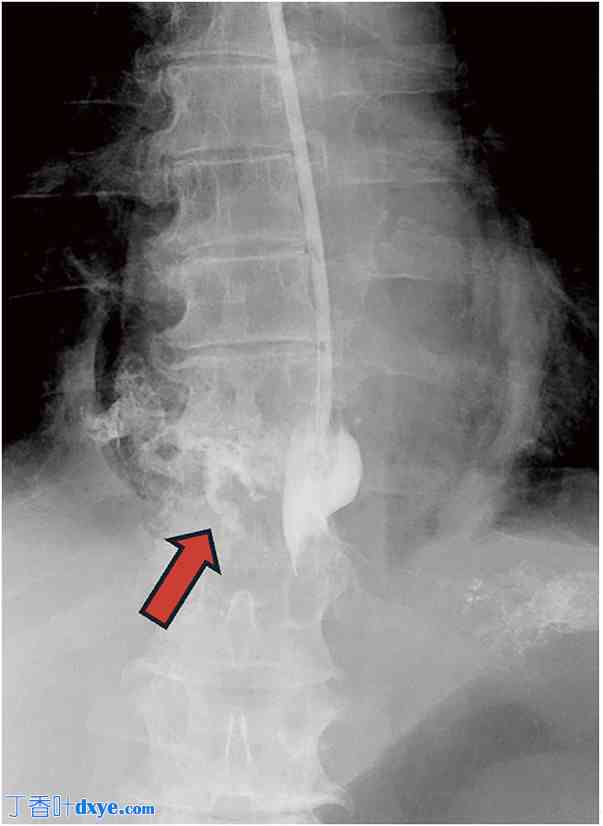

增强CT扫描显示咽部、颈部和纵隔均有气肿,食管下段壁增厚并断裂,右侧胸腔积液,以及气胸(图1)。为了减压和引流,在食管内插入了胃管。对于轻微渗漏,胃管保留在原位进行保守治疗。通过胃管持续注射造影剂显示,造影剂从食管下段右侧渗漏至纵隔(图2),从而证实了自发性食管破裂。因此,进行了急诊手术。由于怀疑穿孔位于食管下段右侧,因此选择了腹腔镜手术。

图2. 造影检查。红色箭头显示造影剂从食管渗漏至纵隔。